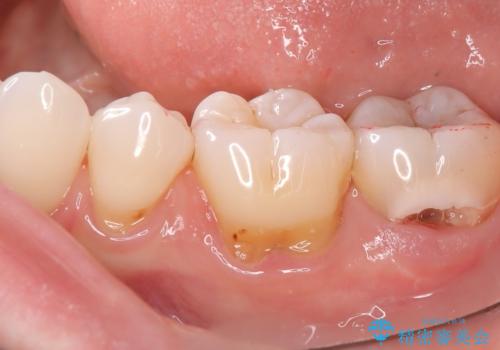

- 主訴:歯に穴が空いていて沁みる

左下7番目の歯の頬側に大きな穴(う蝕によるもの)が空いており、う蝕の範囲が大きく神経を及ぼしている可能性も説明し生活歯髄療法とクラウンでの補綴治療を行うこととなりました。

治療に入る前に歯髄診断を行った結果、正常反応を示しました。

左下7頬側歯頚部に大きくできたう窩内のう蝕を除去していき、生活歯髄療法(間接覆髄法)を行いました。